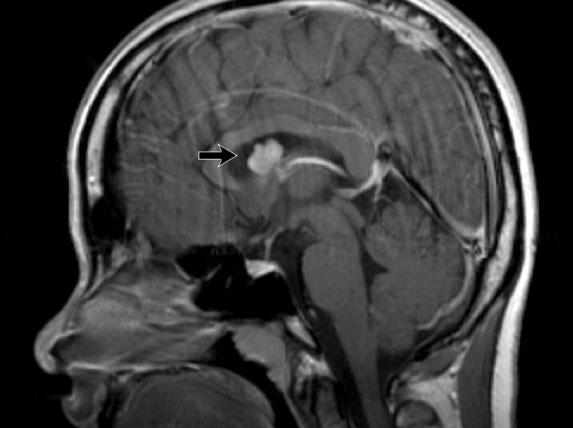

TRÁI: Ngách phễu bình thường của não thất ba (mũi tên xanh), thể vú (mũi tên đỏ). PHẢI: U hamartoma củ xám (tuber cinereum) (mũi tên cong).

U hamartoma vùng dưới đồi (Hypothalamic hamartoma)

U hamartoma vùng dưới đồi còn được gọi là u hamartoma gian não hoặc u hamartoma củ xám.

Đây là tổn thương dị sản chất xám bẩm sinh không phải u tân sinh, khu trú tại vùng củ xám của vùng dưới đồi.

Thường gặp ở trẻ nhũ nhi biểu hiện với động kinh và dậy thì sớm.